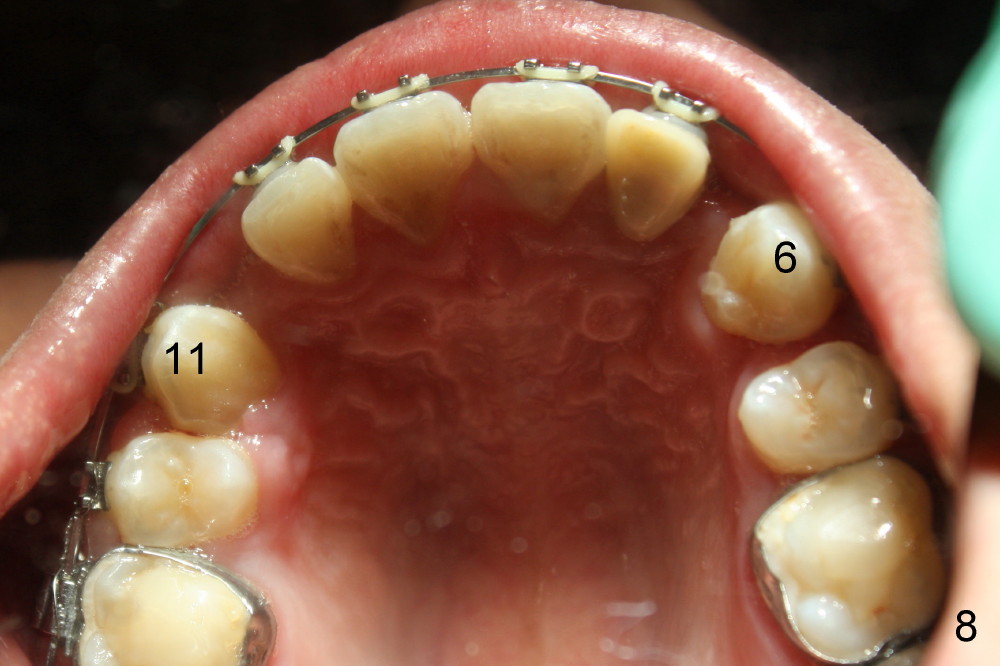

The patient returns 1 month post distalization of the upper incisors (Fig.10-12, 9 months of treatment). Bilateral canine relationship is Class I (Fig.11,12). All needs to be done is to continue distalizing the upper incisors or slightly mesialize the canines if indicated.